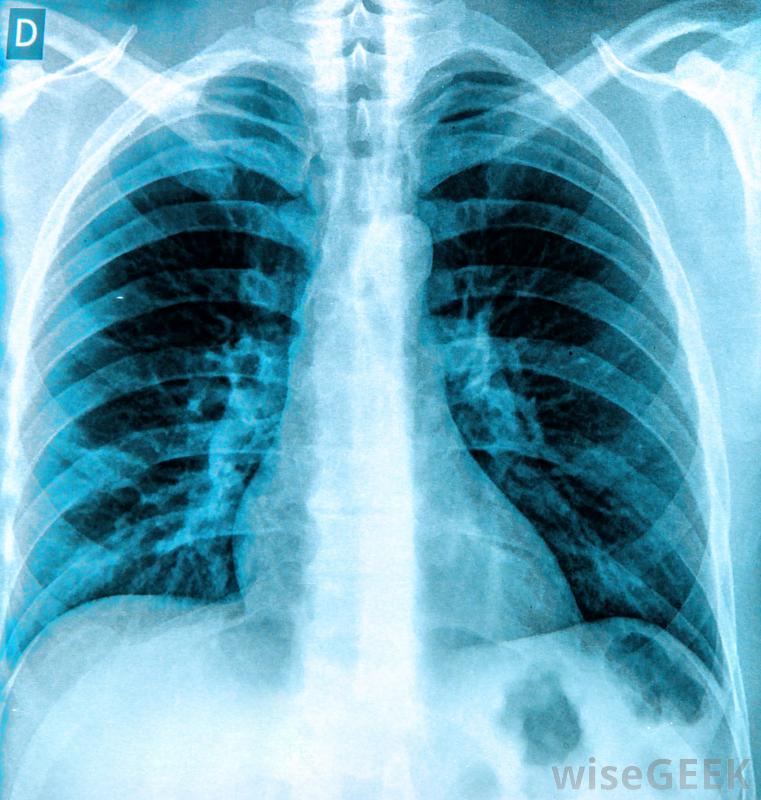

滲出性胸腔積液是一種富含蛋白質的液體在肺部周圍的腔中積聚,這是由肺部及其周圍組織的局部損傷引起的。這種損傷導致細胞開始滲出液體,有時非常迅速。這與滲出性胸腔積液形成對比,系統性過程使血管更具滲透性并增加壓力,導致水樣液體開始漏入胸腔。檢測可以確定是哪種積液,也可以縮小病因。癌癥、創傷,感染是胸腔積液的可能原因。癌癥、外傷和感染都是滲出性胸腔積液的可能原因。在所有這些病例中,局部的細胞損傷會迫使細胞泄漏蛋白質和其他物質。雖然胸膜腔通常有一些液體來潤滑肺部,但當太多液體積聚時,很難呼吸。胸部的一側或兩側可能受累,患者通常會出現呼吸困難、奇怪的呼吸音和問題像紫紺一樣,由于氧合不足,四肢開始發藍。可以通過X光來診斷胸腔積液醫生可以插入針頭或引流管來迅速緩解積液液體的樣本可以被帶到實驗室進行分析,以了解體內發生的情況。如果是滲出性胸腔積液,那么這些樣本中的蛋白質水平會很高。蛋白質和其他物質的平衡也可以為胸腔積液的病因提供線索,就像惡性胸腔積液一樣滲出性胸腔積液的癥狀可能包括呼吸困難滲出性胸腔積液的治療首先要排出多余的液體,這樣病人就可以更容易地呼吸了。一旦病人病情穩定,就可以開始對病因進行評估和治療。治療方案可以包括抗生素等治療感染,以及治療肺部及周圍的癌性腫瘤。在診斷過程中,醫生可能會召集專家來咨詢,因為在診斷過程中會收集到更多關于積液的信息。肺外傷可能會在肺部周圍的空腔中形成富含蛋白質的液體。病理學家可以分析肺部周圍積聚的液體,以便確定原因。